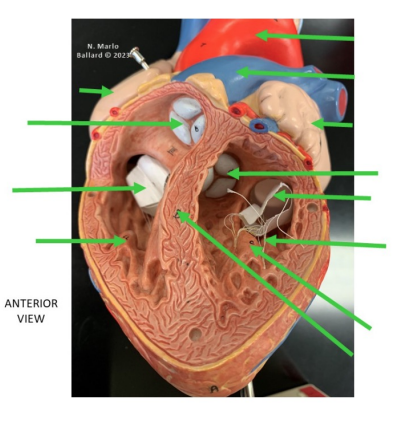

Moderator band

Septomarginal trabecula

Muscular band in the right ventricle

Runs from interventricular septum → anterior papillary muscle

Carries part of the right bundle branch (conduction system)

Helps coordinate ventricular contraction

Fossa ovalis

Depression in the interatrial septum (right atrium)

Remnant of the foramen ovale (fetal circulation)

Function in fetus: allows blood to flow right atrium → left atrium (bypasses lungs)

Closes after birth when pressure in the left atrium increases

Pectinate muscles

Comb-like muscular ridges in the atria

Prominent in the right atrium and auricles (atrial appendages)

Help increase force of contraction without greatly increasing mass

Located anterior to the crista terminalis in the right atrium